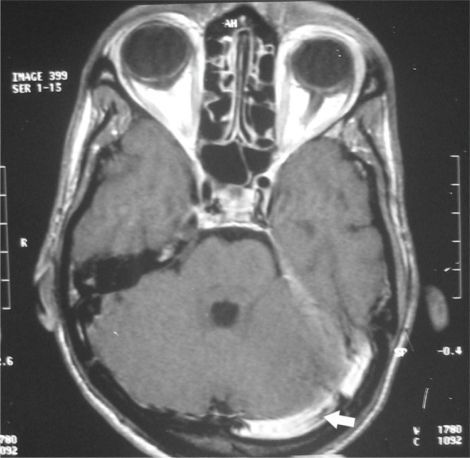

Lateral sinus thrombosis is a rare complication of middle ear infection. This complication was fairly common in pre-antibiotic era, however, in present age, it may occur in individuals with advanced age and chronic middle ear infection. Lateral sinus thrombosis presents with: - Picket-fence fever - Earache - Headache - Vomiting - Neck stiffness and pain - Papilledema The cornerstone of the management of lateral sinus thrombosis is antibiotics and surgery. Although not a part of standard care, anticoagulants are also beneficial in improving prognosis. Reference: https://www.ncbi.nlm.nih.gov/pmc/articles/PMC3033149/